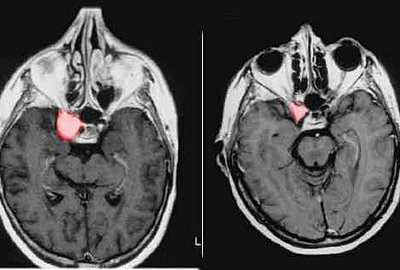

Whiplash Injuries Can Be Visible By Functional Magnetic ...

A 27-year-old woman was hit by another car from the right side. A computed tomography scan did not show skeletal injury, luxation or herniation. Soon after the accident, she developed headaches and sensitivity to light and noise that nausea and severe dizziness. After three days, ... Visit Document